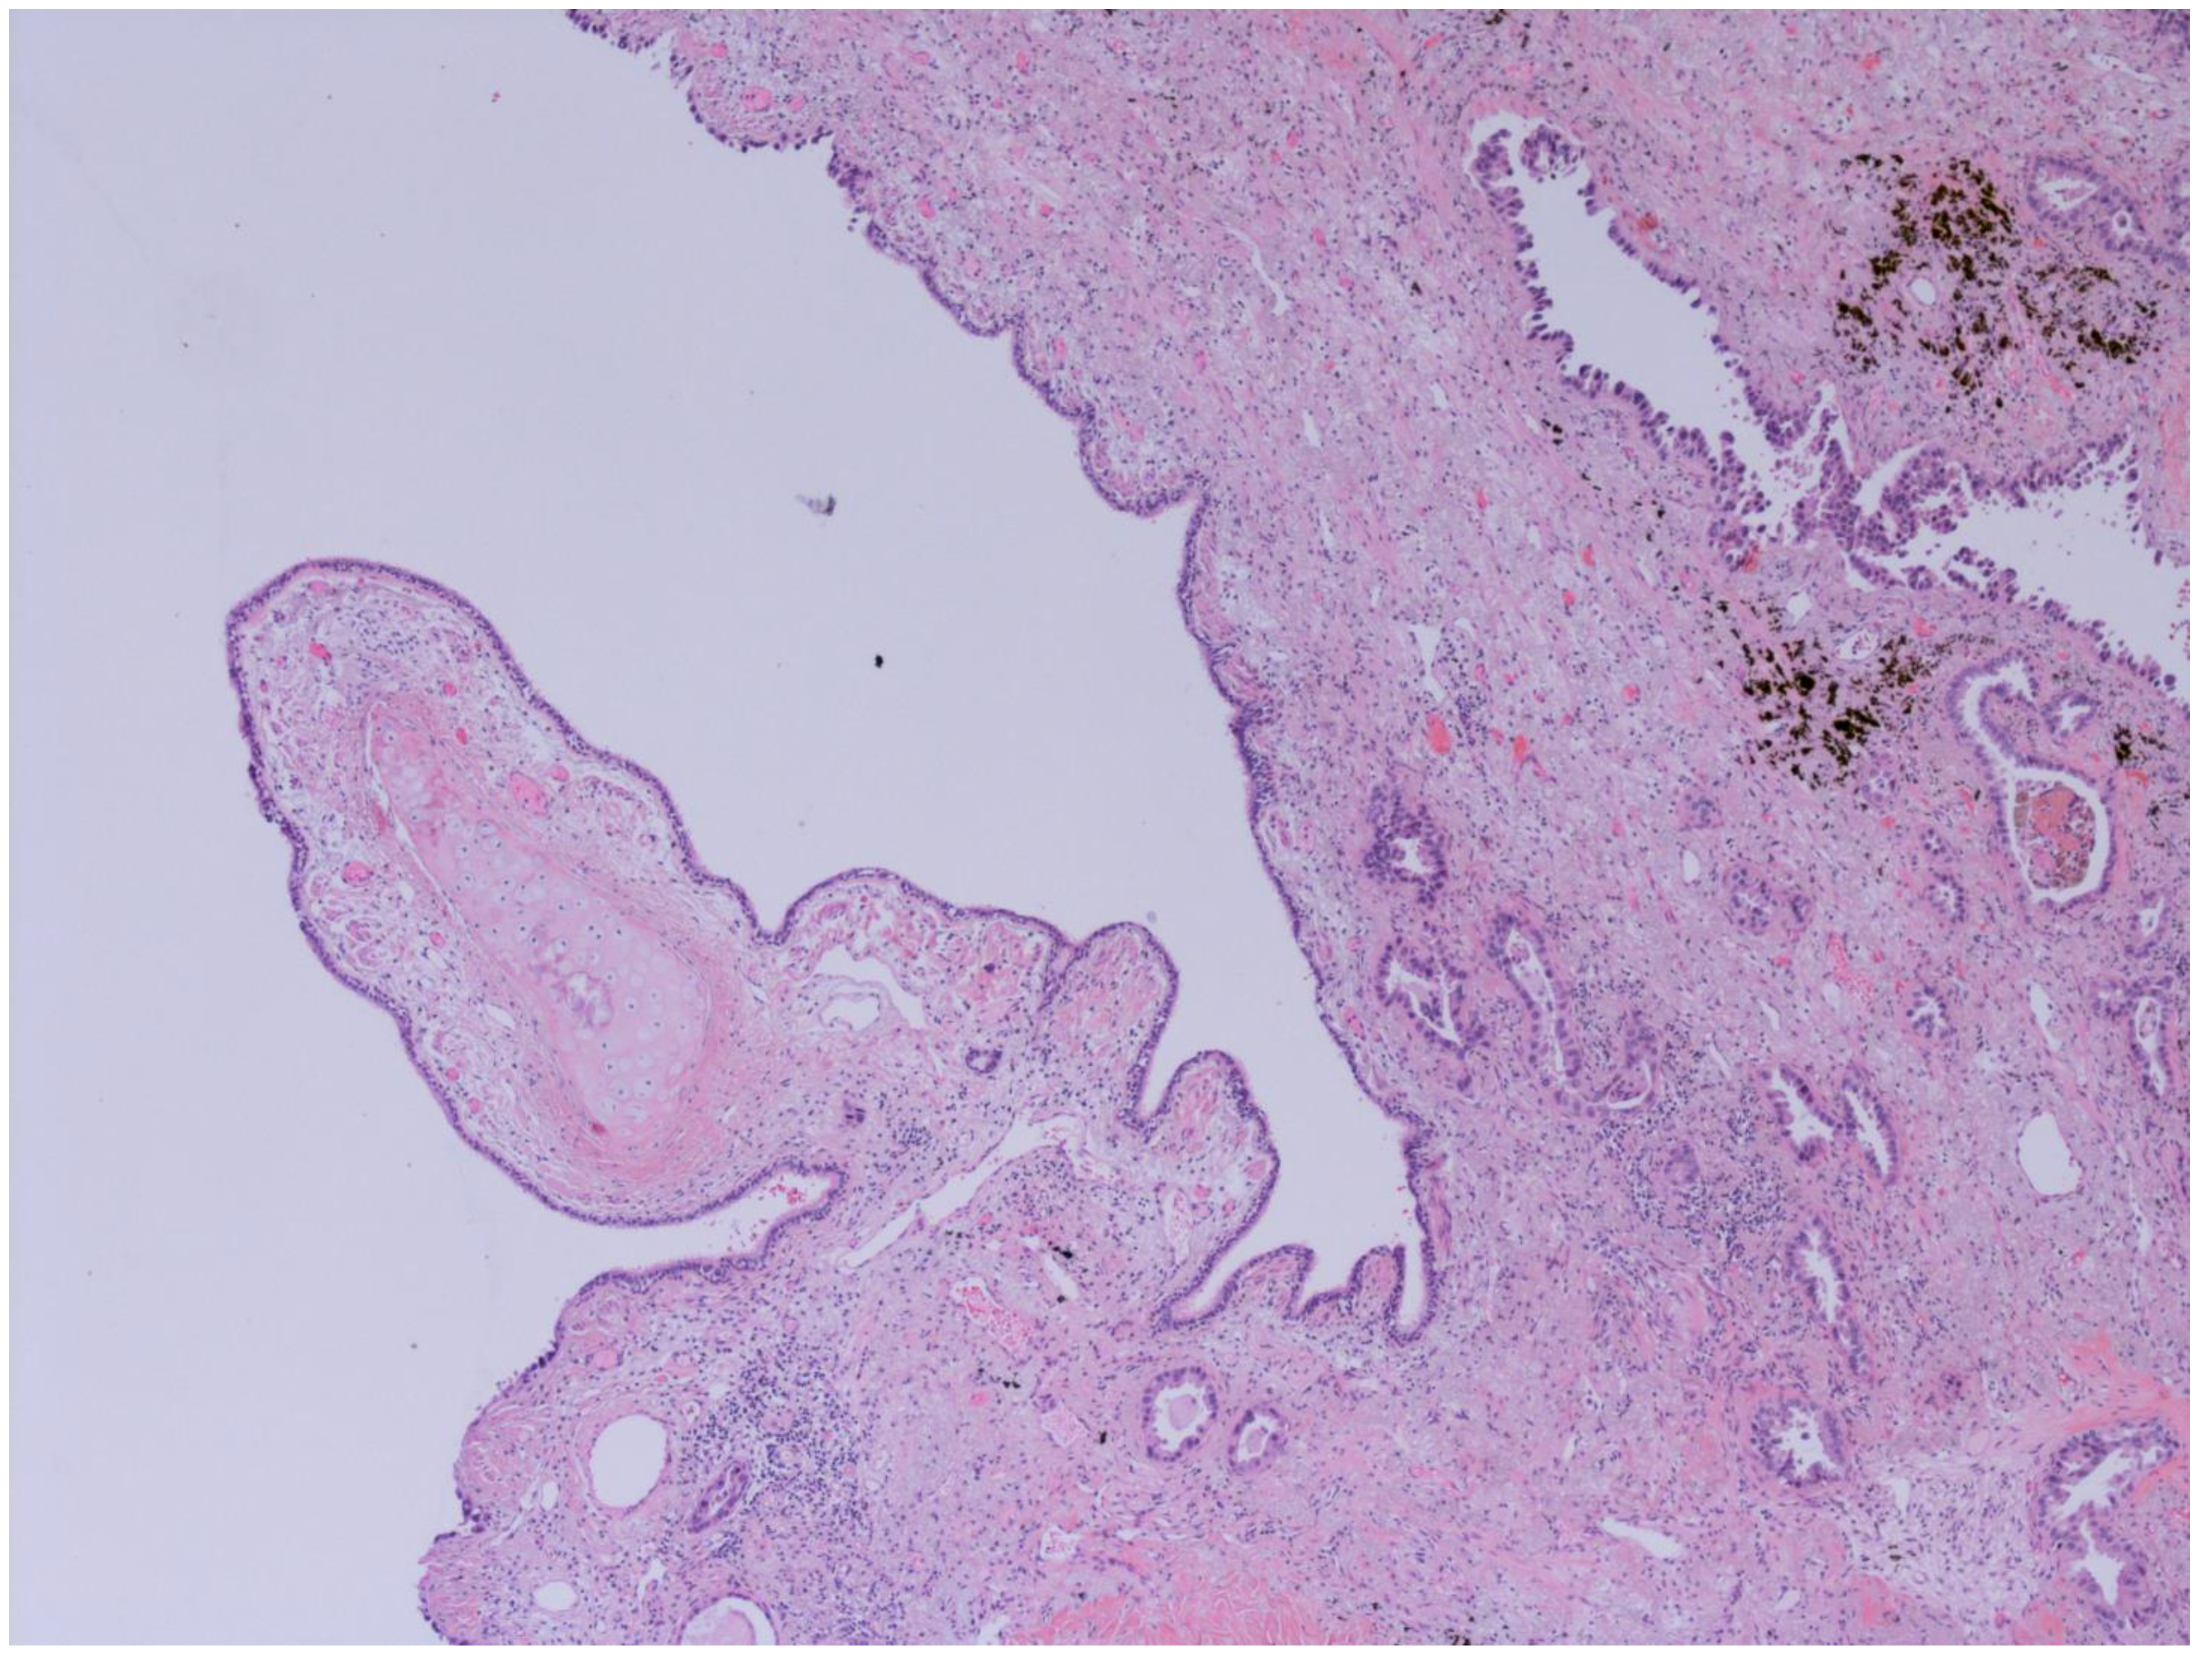

3.7. Histological Subtypes of Lung Cancer in NCFB